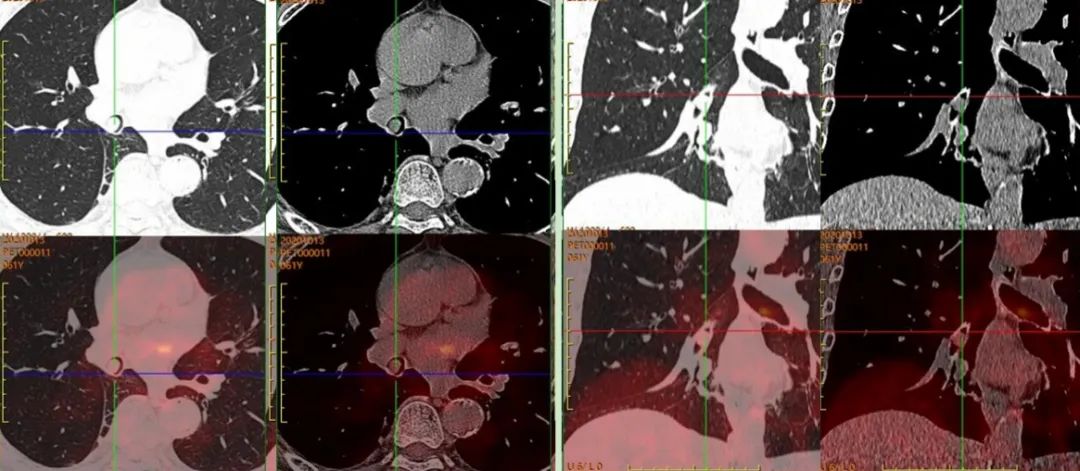

患者于上級醫(yī)院行氣管鏡檢查,病理考慮為“惡性腫瘤”。后來我院行PET/CT,完善治療前檢查。

圖2,PET/CT示右肺中間段支氣管結節(jié),早期SUVmax約1.8,延遲SUVmax約1.9,呈低代謝表現(xiàn);全身其余部位未見惡性腫瘤證據(jù);考慮為孤立的、單發(fā)的支氣管腔內腫瘤,建議患者病理檢查。

患者后于上級醫(yī)院手術治療,術后病理為“支氣管錯構瘤”。